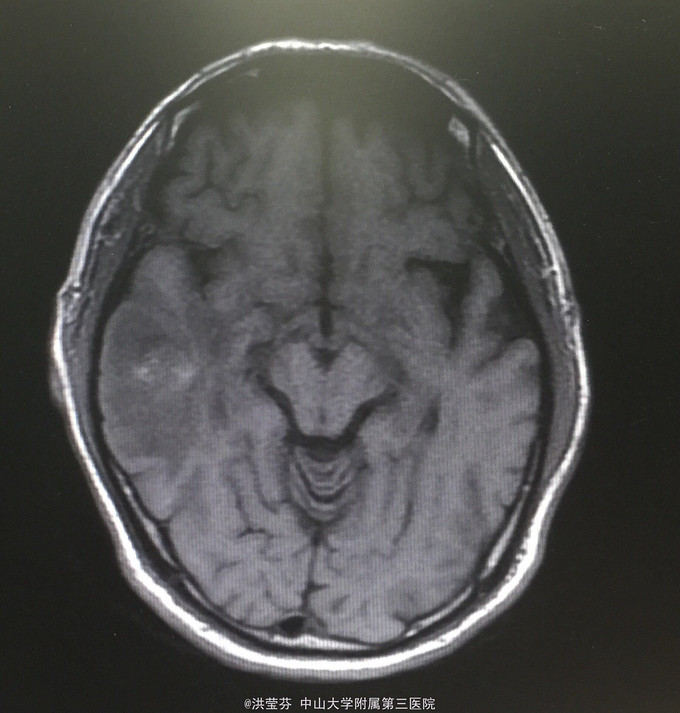

查体:KPS 60分,BSA 1.83m2,T 38.5℃,全身浅表淋巴结未触及明显肿大,胸壁可见浅表静脉曲张,呼吸急促,左下肺、右中下肺呼吸音明显减弱,其余肺野呼吸音促,可闻及少许实性啰音,心率110bpm,律齐,腹软,全腹无压痛、反跳痛,未扪及明显包块,肝脾肋下未触及,移动性浊音(——),肠鸣音正常,4次/分,双下肢无凹陷性水肿。 辅助检查:血常规无特殊,生化转氨酶稍升高,低钠低氯,CRP 227.9mg/L,凝血四项:Fib 8.14g/L。复查胸部CT提示:1.胸腺癌并纵膈淋巴结及双肺多发转移瘤,右心房、上腔静脉受侵并癌栓形成,病变较前进展。2.双肺炎症,以右肺为著。3.双侧胸腔及心包积液。上腹部CT提示:1.下腔静脉早显并肝表面多发侧支形成,考虑右心流出道阻塞所致;腹壁静脉曲张。头颅MR提示右侧颞叶强化灶,结合病史,考虑转移瘤,伴瘤灶少量出血可能,瘤周脑水肿。